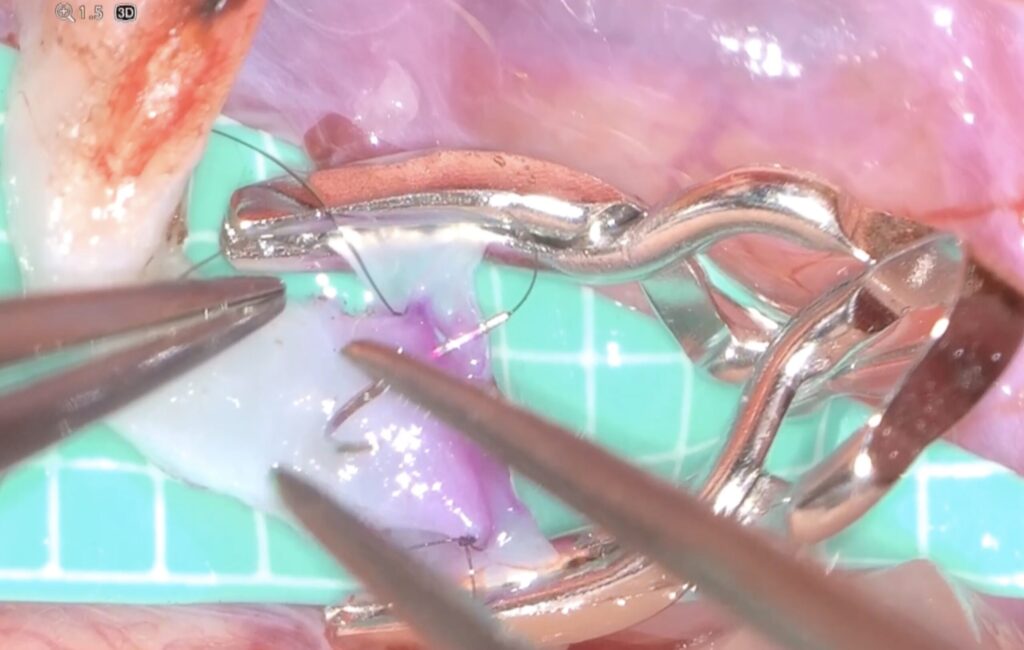

外視鏡を用いると吻合時にはデジタルズームをフットスイッチで入れると瞬時に高拡大にできます。

糸が通ったら、また瞬時にデジタルズームを切ります。

次の針はまち針のように通してあり、しかも糸は常に繋がっていますので、針は無くなりません(Needle parking mehtod)